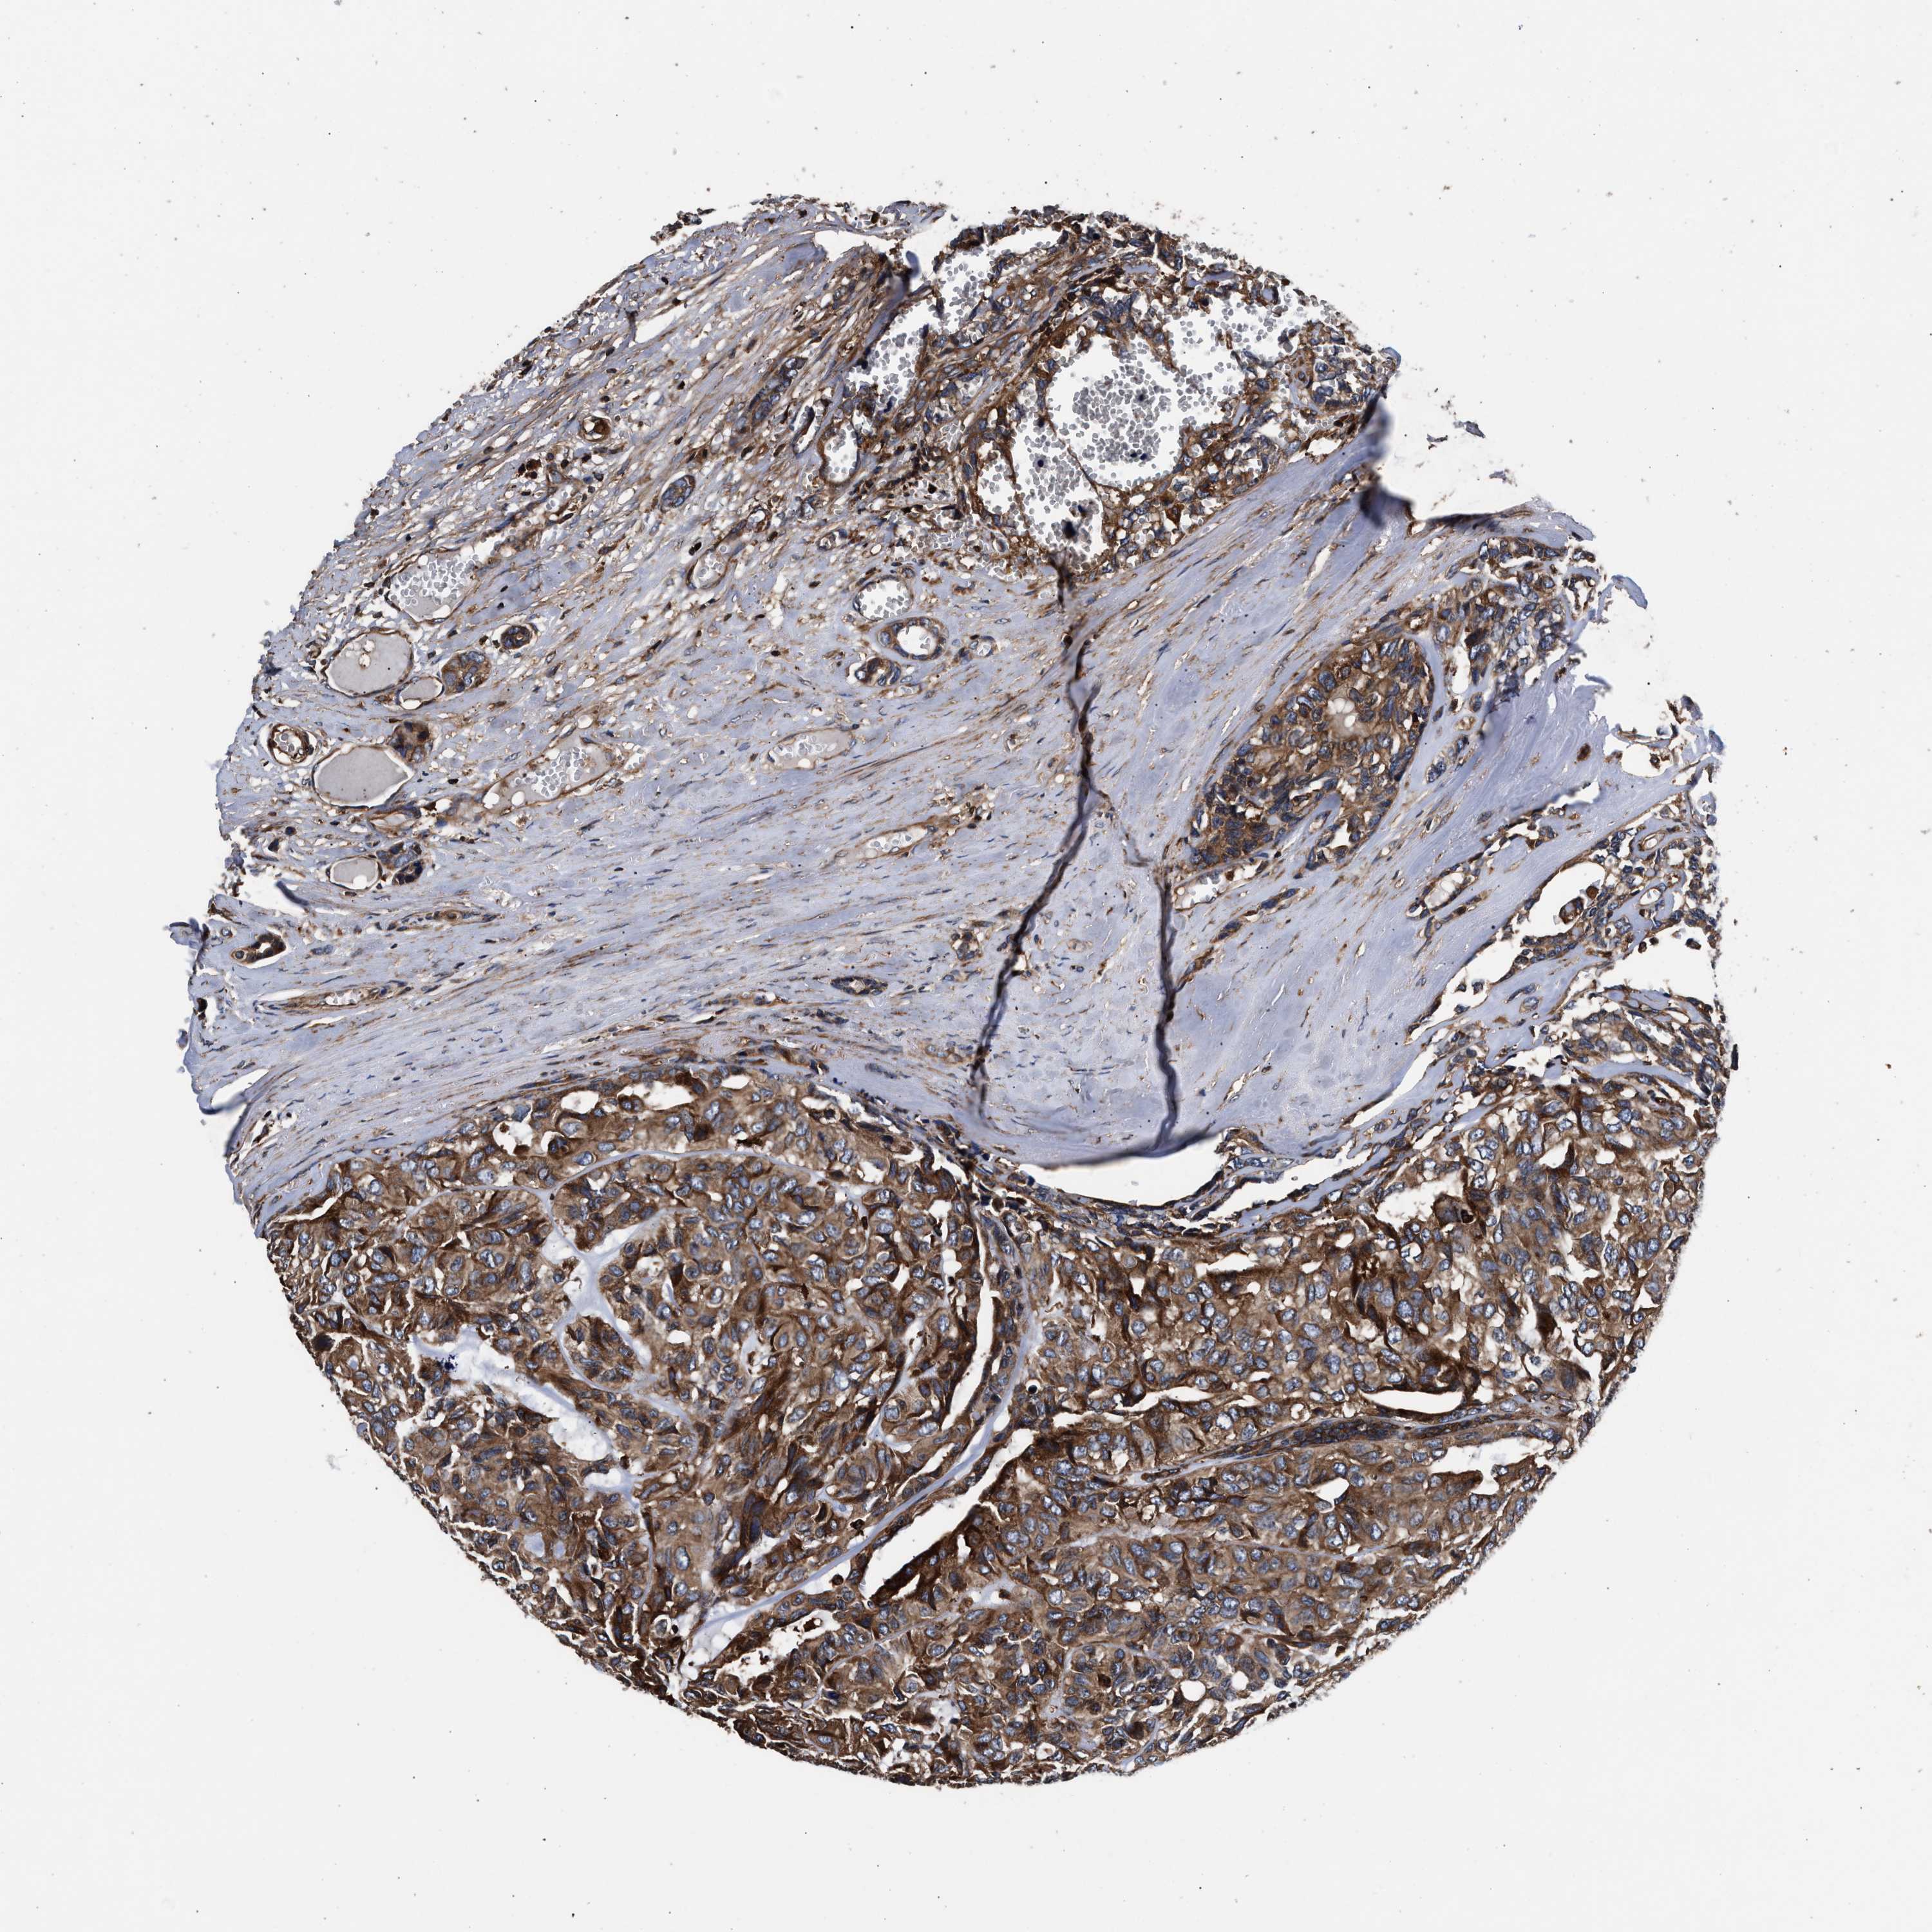

HEAD AND NECK CANCER - Protein expressioni

A mouse-over function shows sample information and annotation data. Click on an image to view it in a full screen mode. Samples can be filtered based on level of antibody staining by selecting one or several of the following categories: high, medium, low and not detected. The assay and annotation is described here.

Antibody stainingi

Antibody staining in the annotated cell types in the current human tissue is reported as not detected, low, medium, or high, based on conventional immunohistochemistry profiling in selected tissues. This score is based on the combination of the staining intensity and fraction of stained cells.

Each image is clickable and will lead to virtual microscopy that enables deeper exploration of all samples and also displays staining intensity scores, fraction scores and subcellular localization as well as patient and tissue information for each sample.

Antibody HPA021176

Antibody HPA021177

Antibody HPA027736

Staining

High

Medium

Low

Not detected

Intensity

Strong

Moderate

Weak

Negative

Quantity

>75%

75%-25%

<25%

None

Location

Nuclear

Cytoplasmic/membranous

Cytoplasmic/membranous,nuclear

Squamous cell carcinoma, NOS

Squamous cell carcinoma, metastatic, NOS

Adenocarcinoma, NOS

Adenoma, NOS